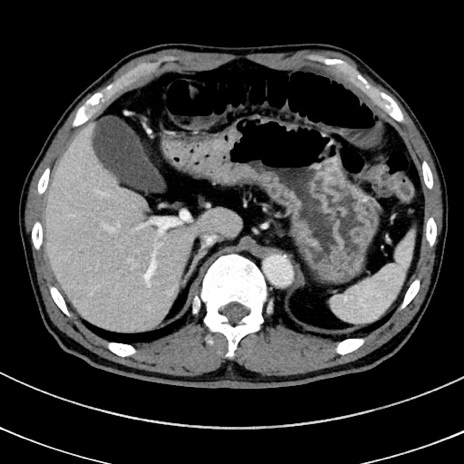

症例8(横断像)

【症例】 60歳代男性

【主訴】 黒色吐物

【現病歴】 4日前から嘔気自覚、2日前の朝食後にも嘔気あり、自分で手で嘔吐反射起こし嘔吐したところ血が混ざっていたため受診。

【既往歴】 5年前汎発性腹膜炎を伴う急性虫垂炎で手術、高血圧、前立腺肥大症、高脂血症

【身体所見】 腹部正中に手術癩痕あり 腹部平坦・軟圧痛なし膨満感あり

【データ】WBC 8400、CRP 4.54